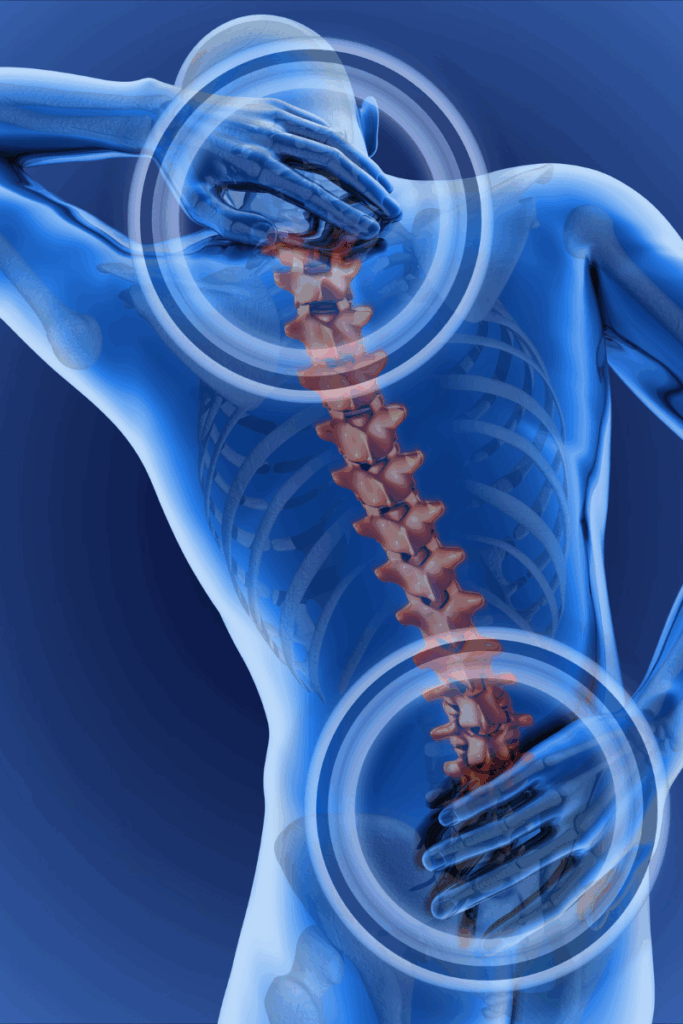

Lower back pain is one of the most common reasons people seek medical care. It can range from a dull ache to sharp, debilitating pain that limits your ability to work, sleep, or enjoy daily activities. Whether caused by injury, poor posture, degenerative conditions, or muscle strain, lower back pain can significantly impact your quality of life.

Lower back pain may be related to a number of diagnoses, and physical therapy is proven to help with many of them, including:

- Lumbar strain or sprain

- Herniated or bulging discs

- Degenerative disc disease

- Sciatica or nerve impingement

- Spinal stenosis

- Post-surgical rehabilitation

- Chronic lower back pain from poor posture or sedentary lifestyle